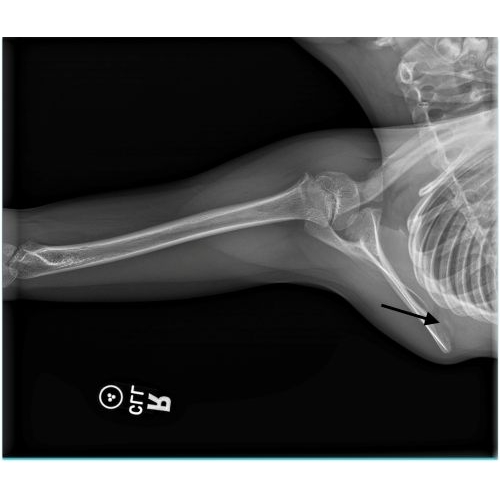

| Monkey Bar Mishap: A Unique Scapulothoracic Injury And Presentation - Page #3 | |||